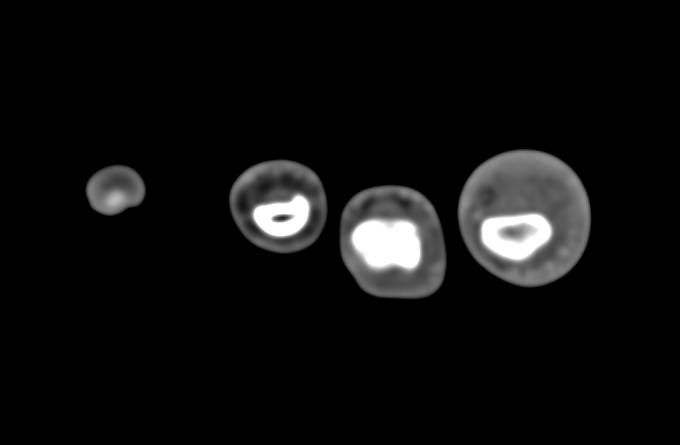

Osteosarcoma of the Humerus